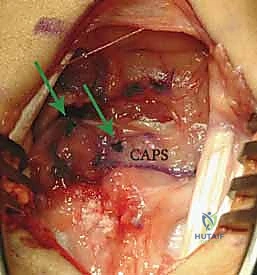

* This image demonstrates the repair augmentation with the ulnar-based capsular (CAPS) flap. Notice the suture anchor knots (arrows) and the placement of the distal suture anchor at the scaphoid, reinforcing the dorsal intercarpal ligament footprint.